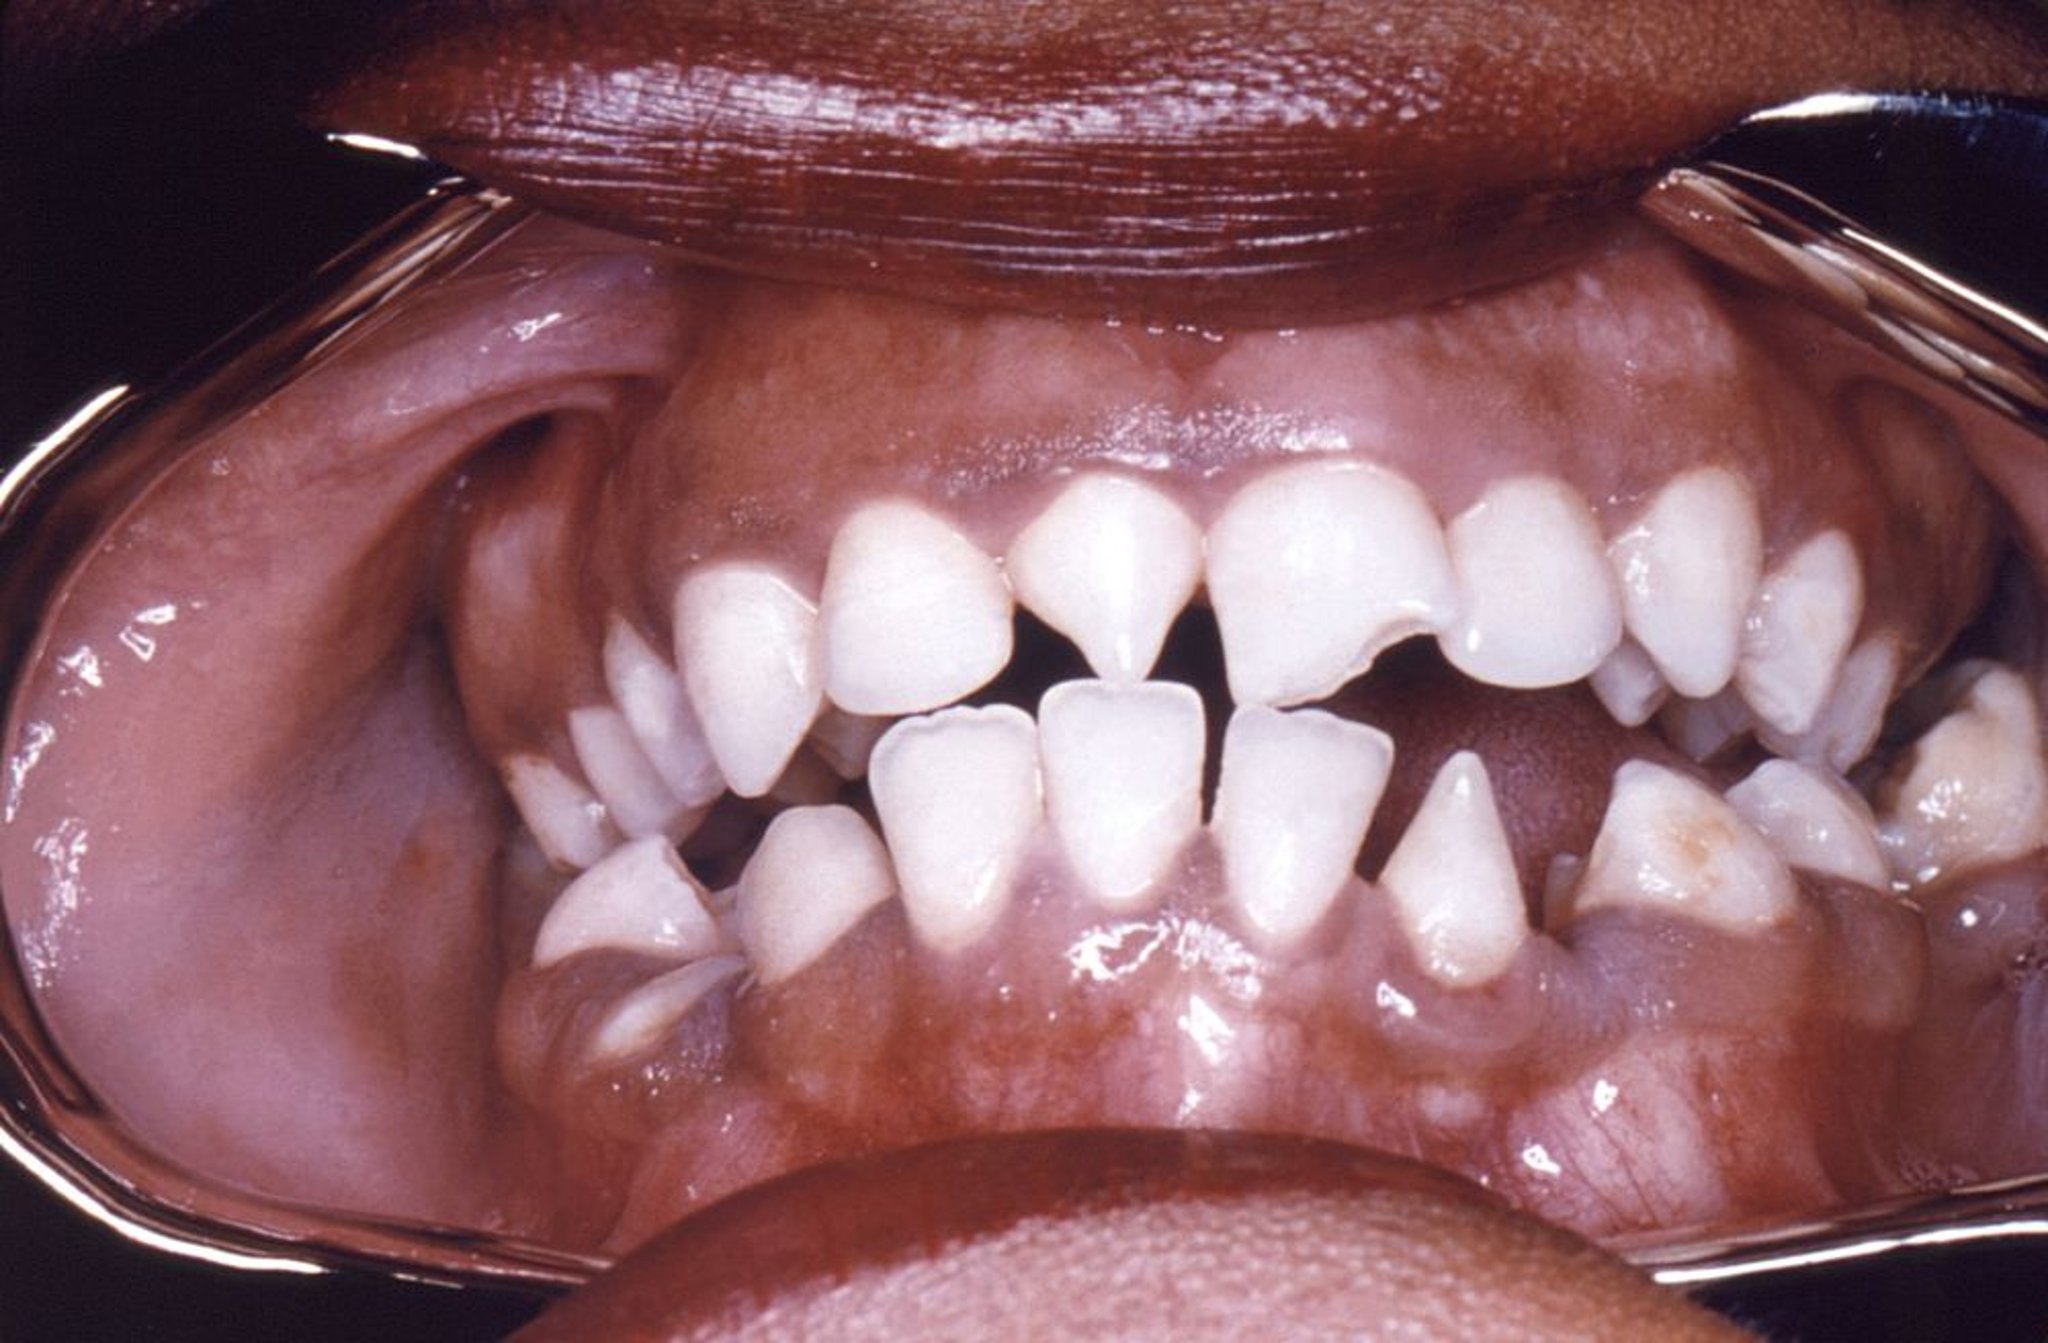

Incisivi di Hutchinson

Questa foto mostra una deformità a forma triangolare degli incisivi superiori di destra e inferiori di sinistra causati da sifilide congenita.

Image courtesy of Robert E. Sumpter via the Public Health Image Library of the Centers for Disease Control and Prevention.